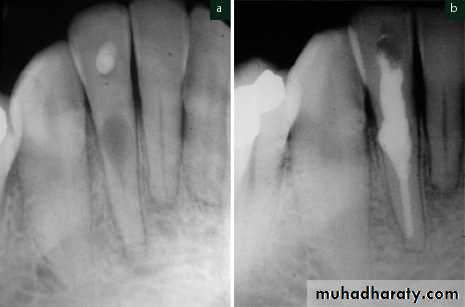

• Usually asymptomatic, recognized clinically through routine radiograph (especially in the root)• Pain occurs in cases of perforation of crown.

• “Pink Tooth” is the pathognomic feature of internal root resorption (especially in the crown).

• Clinically:“Pink Tooth” appearance• Radiographic changes:

– Radiolucent enlargement of pulp canal

– Original root canal outline distorted

• Pulp extirpation stops internal root resorption.

• Surgically treatment is indicated if conventional treatment fails.